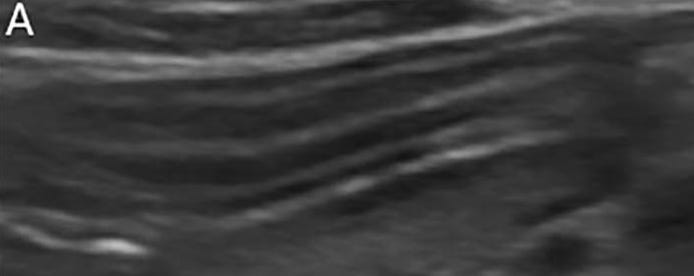

Imagen ecográfica normal de la pared intestinal:

La ecografía en modo B en perros con EIC sirve principalmente para excluir otros trastornos subyacentes.

El engrosamiento de la pared intestinal es común en la EIC, pero no es predictivo de inflamación.

Los cambios en la ecogenicidad mucosa, la corrugación del ID y una puntuación ecográfica acumulada elevada se asocian con EIC sintomática, pero no con la gravedad histopatológica.

La mucosa del ID hipoecogénica normal con EIC tiene ≥80% de sensibilidad y especificidad para la EIC-FR, pero los hallazgos se solapan entre los subtipos de EIC.